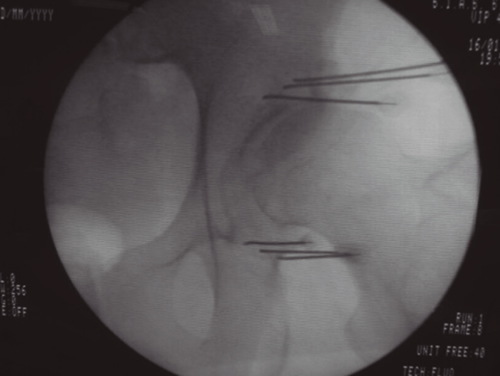

Aunque la articulación de la cadera se afecta con menos frecuencia que la rodilla, también parece despertar menos curiosidad e interés de las publicaciones, pues son muchas menos que sobre la rodilla. La inervación de la cadera está bien estudiada (24,25,26). El resumen de todas estas publicaciones es que la cápsula articular de la cadera recibe inervación en su cara anterior de los nervios femoral (cuadrante supero externo) y obturador en el cuadrante ínfero interno. Se ha demostrado que la denervación de la cápsula articular en la cara anterior produce un alivio del dolor en los pacientes con coxartrosis avanzada que no pueden ser tratados con una prótesis total debido a diferentes factores (edad avanzada, comorbilidades o riesgo quirúrgico elevado). Esquematizando mucho la inervación de la cara anterior de la cadera resumiría en que las ramas articulares del femoral se localizan en la parte superior y externa del cotilo femoral, mientras que las ramas articulares del obturador se localizan en la parte inferior sobre la rama descendente del isquión en su unión con el borde inferior del cotilo. La primera publicación describiendo una técnica de denervación con radiofrecuencia de la cara anterior de la cápsula articular de la cadera se produce en 2001 (27), en el que Kawaguchi describió una técnica con una aguja colocada en el borde anterolateral del cotilo para lesionar las ramas del nervio femoral, y otra en la parte inferior en la unión entre la parte externa de la rama pubiana y la descendente del isquión para lesionar las ramas del obturador mediante radiofrecuencia térmica; obtiene buenos resultados en disminuir el dolor en pacientes con coxartrosis. En los años siguientes se siguen publicando trabajos con un abordaje similar al de Kawaguchi, con control radiológico o con control ecográfico (28,29,30), así como algunas series de casos con radiofrecuencia pulsada (31). En 2018 se publicó una revisión de la evidencia que concluye que ninguno de los trabajos publicados es un RCT y que es necesaria su realización con una metodología de alta calidad para poder valorar el papel de estas técnicas. En 2008 (32)una publicación hace una valoración de la anatomía radiológica del nervio obturador, analizando la dificultad que tiene lesionar todas las posibles variaciones anatómicas de las ramas articulares del obturador con una sola aguja, además de analizar la dificultad que presenta el abordaje anterior de estas ramas debido a la presencia del paquete vásculo-nervioso femoral, que se interpone en el trayecto de las agujas, recomendando introducirlas de manera anterolateral con un ángulo de al menos 70° con el plano vertical. Termina proponiendo la realización de tres lesiones para asegurar la neurotomía de la mayoría de las ramas articulares. Basándonos en este artículo, desarrollamos una variación de la técnica de Kawaguchi en la que utilizamos tres agujas en la zona superoexterna del cotilo, y otras tres agujas en la parte inferior en la rama ascendente del isquión, introducidas de manera lateral con un ángulo al menos de 70° respecto al plano vertical, y realizando una lesión en empalizada con radiofrecuencia térmica bipolar entre cada dos agujas (Figura 3), obteniendo buenos resultados en más del 60 % de los pacientes tratados, que fue objeto de una comunicación a un congreso de la SED. Estas técnicas tienen que ser validadas en cuanto a su reproducibilidad y resultados, careciendo en estos momentos de evidencia, y de la estandarización de las referencias anatómicas y radiológicas para su realización (33).

Fig. 3.

La neurotomía por radiofrecuencia de las ramas articulares de los nervios femoral y obturador es una técnica no estandarizada, cuyas referencias anatómicas y radiológicas están todavía sin establecer y que precisarán de la realización de RCT de calidad para poder conseguir datos de evidencia sobre su utilidad. En mi opinión la realización de lesiones en empalizada con dos o tres agujas puede mejorar la posibilidad de lesionar la mayoría de las ramas sensoriales que, debido a las variaciones anatómicas, pueden ser difíciles de lesionar con una sola aguja. El principal peligro y complicación de esta técnica es la aparición de hematomas por punción accidental de la arteria femoral, si el abordaje se hace de manera vertical. La técnica se puede realizar con control radiológico o ecográfico, ofreciendo la ecografía la ventaja de poder visualizar el paquete vasculonervioso femoral.